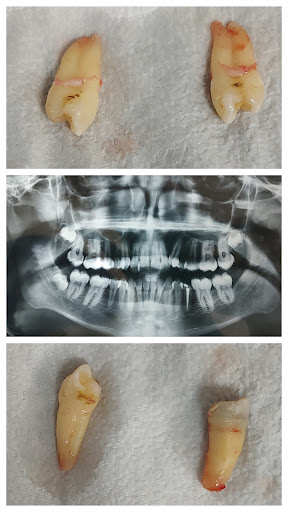

A visit away solution to your Any tooth and gums related problems. Root canal treatment, Asthetic and cosmetic treatments, Orthodontic treatments, teeth cleaning and whitening are done with best material and instruments. For permanent teeth Implants are available in affordable price it can be done for a single missing tooth or for all teeth in o...

Gallery